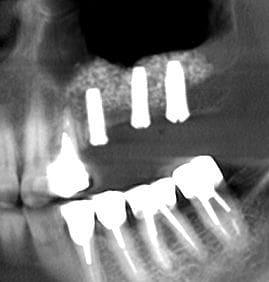

pour illustrer cette utilisation du bioactys, voici un cas (ce matin, mise en focntion des implants à 7 mois post_op)

la chir est résumée en vidéo ici:

ici c'est un mix (pour un impératif perso): en 25 un easy-implant master s puis 2 dentium superline.

Le easy c'est du sablé au corindon et les dentium sablés-mordancés SLA http://www.dentogem.com/viewpage.php?pageid=48

j'ai donc procédé à la mise en fonction ce matin, 7 mois après l'intervention. Mise en place de piliers de cicatrisation assez hautes et surtout de diamètres en adéquation avec une PM et 2M. je prends l'empreinte dans 3 semaines , la gencive sera belle autour des piliers.

je vous mettrai les photos finish.